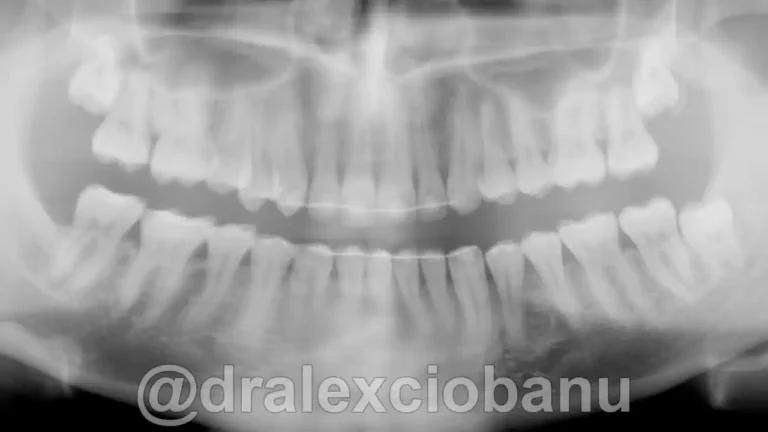

Caso clinico MORSO PROFONDO prima Caso clinico MORSO PROFONDO dopo

PRIMA

DOPO